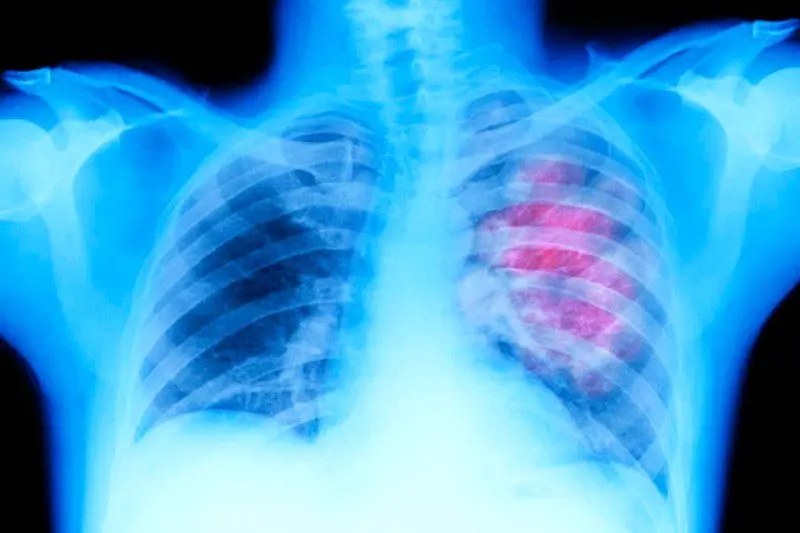

این سیستم برای کار در کنار سیستم‌های هوش مصنوعی موجود طراحی شده است، که اغلب برای تفسیر تصاویر پزشکی مانند اشعه ایکس قفسه سینه یا ماموگرافی استفاده می‌شوند. به عنوان مثال، اگر یک ابزار هوش مصنوعی پیش‌بینی‌کننده در حال تجزیه و تحلیل ماموگرافی باشد، CoDoC قضاوت می‌کند که آیا گزارش ابزار به اندازه کافی قوی است که برای تشخیص به آن تکیه کند یا در صورت عدم اطمینان، پای انسان را به مسئله باز کند.